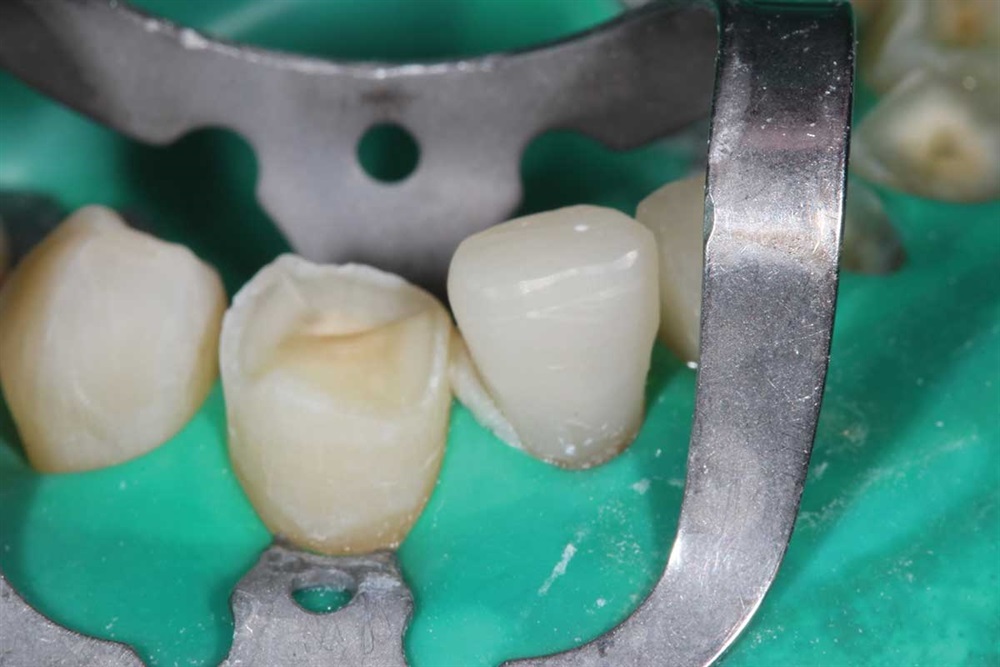

Show Your Work

Fig. 27: Starting the maxillary teeth with 90N, rubber dam and Premier Cure-Thru contoured matrix band. Incisal view.